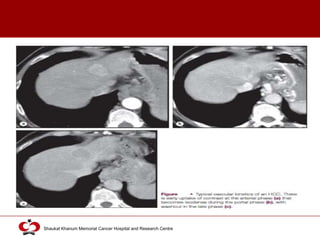

Helical / Multislice spiral / multiphasic CT

 More accurate than US

 Multiphasic

 Without contrast

 With Contrast:

 Arterial (25-50s)

 Portal (60-65s)

 Equilibrium (130-180s)

CT scan: features

 Usually hypodense

 Spontaneous hyperdense (2-20%): iron overload or

fatty infiltration

 Early uptake of contrast with mosaic shape pattern

 Sharply diminished density in portal phase

 Washout during late phase

 Variable vascularity depending on tumor grade

 Capsule: Peripheral enhanced thickening in portal or

late phase

 Intratumoral arterioportal fistula

 Early enhancement of portal branches

 Triangular area distal to tumor with contrast enhancement

different from adjacent parenchyma